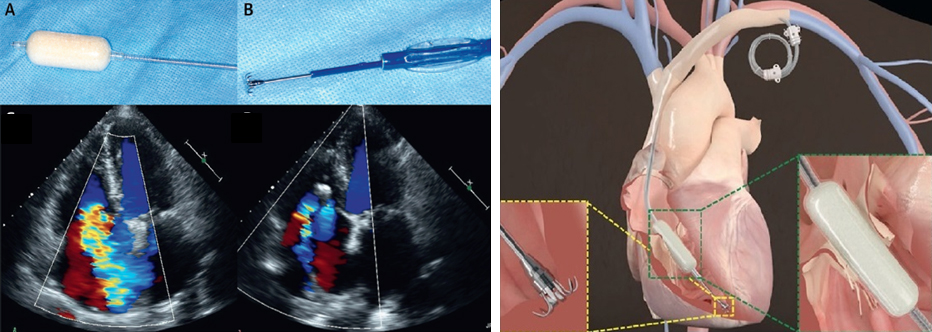

그림 1. CAVI with Tric Valve Device

(A)Spacer. (B)Anchoring system

그림 4. The FORMA Repair system